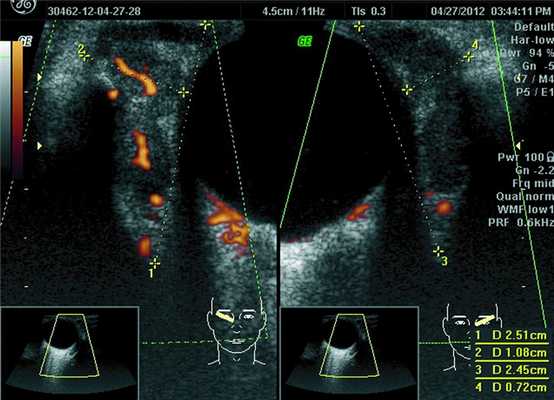

При ультразвуковом исследовании орбит 32 пациентов у 23 было выявлено увеличение линейных и объемных размеров слезных желез (рис. 1), Рисунок 1. Эхограмма глазного яблока и слезной железы в косой проекции с правой и левой стороны. На ультразвуковом срезе размеры слезных желез по глубине и ширине значительно увеличены (OD — 2,51 см на 1,08 см, OS — 2,45 см на 0,72 см). Видны извитые сосудистые цветовые карты. Внутри слезной железы визуализируются обширные сливные зоны разряжения. что сопровождалось изменениями функции органа и развитием синдрома сухого глаза в 8 случаях. Увеличение слезных желез в 19 случаях было парным, в 4 — односторонним.

с sph -10,0 дптр=0,5; ВГД OU=18 мм рт. ст. (по Маклакову). Поля зрения, цветоощущение — в пределах нормы. OD — положение правильное, подвижность в полном объеме. OS — смещение глазного яблока вниз, ограничение его подвижности во всех направлениях и увеличение диплопии при отведениях. Сужение глазной щели слева, птоз (рис. 1 A). Увеличение размеров слезной железы слева (рис. 1 B). При биомикроскопии и осмотре глазного дна обоих глаз признаков воспалительного процесса (увеита) не выявлено.